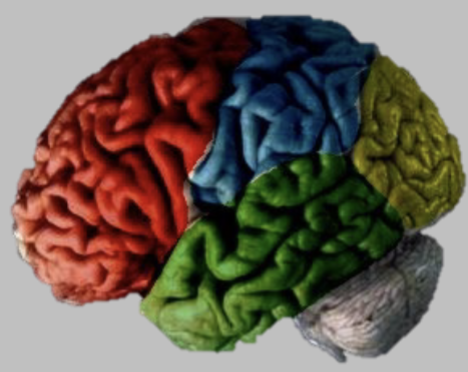

Neocortex — Frontal Lobes (Red)

Planning & executive functions (inhibitions, self control – inhibition, ability to plan for the future, memory)

Primary motor cortex - neurons send axons to spinal cord to send signals to muscles to move – one of main output centre in brain - voluntary movements

Neocortex — Parietal Lobes (Blue)

Perception and understanding of space around us – represents space for action

Somatosensory cortex - when neurons are stimulated/activated you will feel touch

Neocortex — Temporal Lobes (Green)

Memory and language

Has the hippocampus

Primary auditory cortex - auditory information arrives from the thalamus here

Taste and smell

Neocortex — Occipital Lobes (Yellow)

Vision - recognise things, people, understand how the vision experience is organised